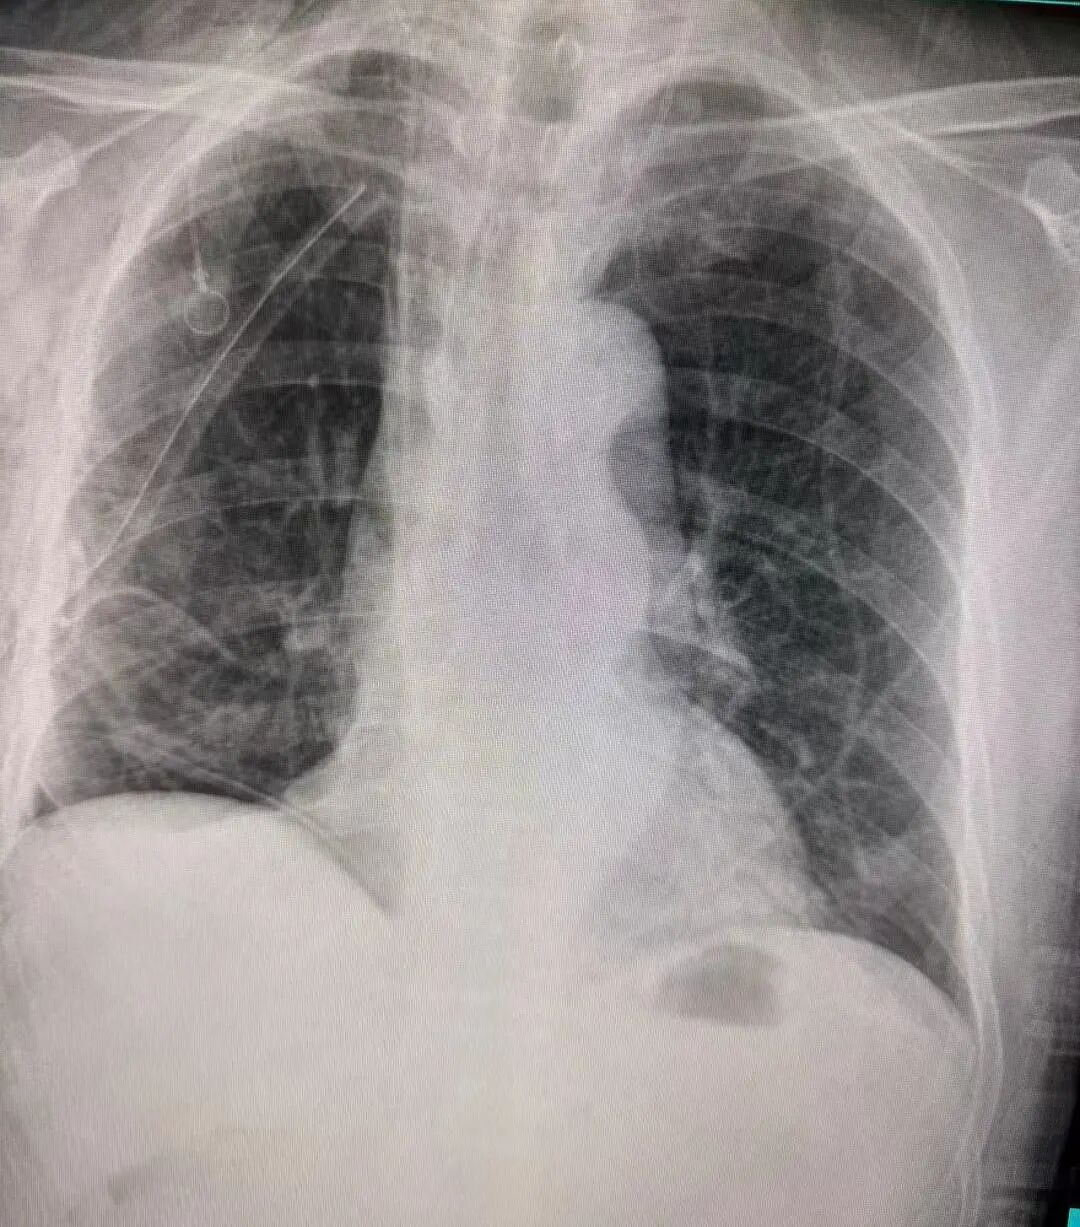

治疗前胸片可见右肺门区域明显占位阴影,肿瘤体积较大,位置深、靠近中心大血管